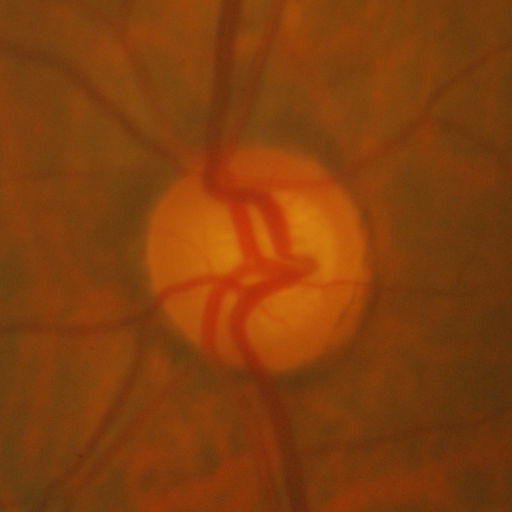

4.2 Datasets and Metrics

We evaluate on widely used datasets for optic disc and cup segmentation. Following previous studies, REFUGE [19] is used as the source domain, while RIM-ONE-r3 [5], Drishti-GS [21], and REFUGE validation [19] (open domain) are used as targets. The splits are 320/80 (REFUGE), 90/60 (RIM-ONE-r3), and 50/51 (Drishti-GS) for training/testing, with 80 open-domain images. As in [29], fundus images are ROI-cropped to . We report Dice coefficient (DICE) and Average Symmetric Surface Distance (ASSD) as evaluation metrics.